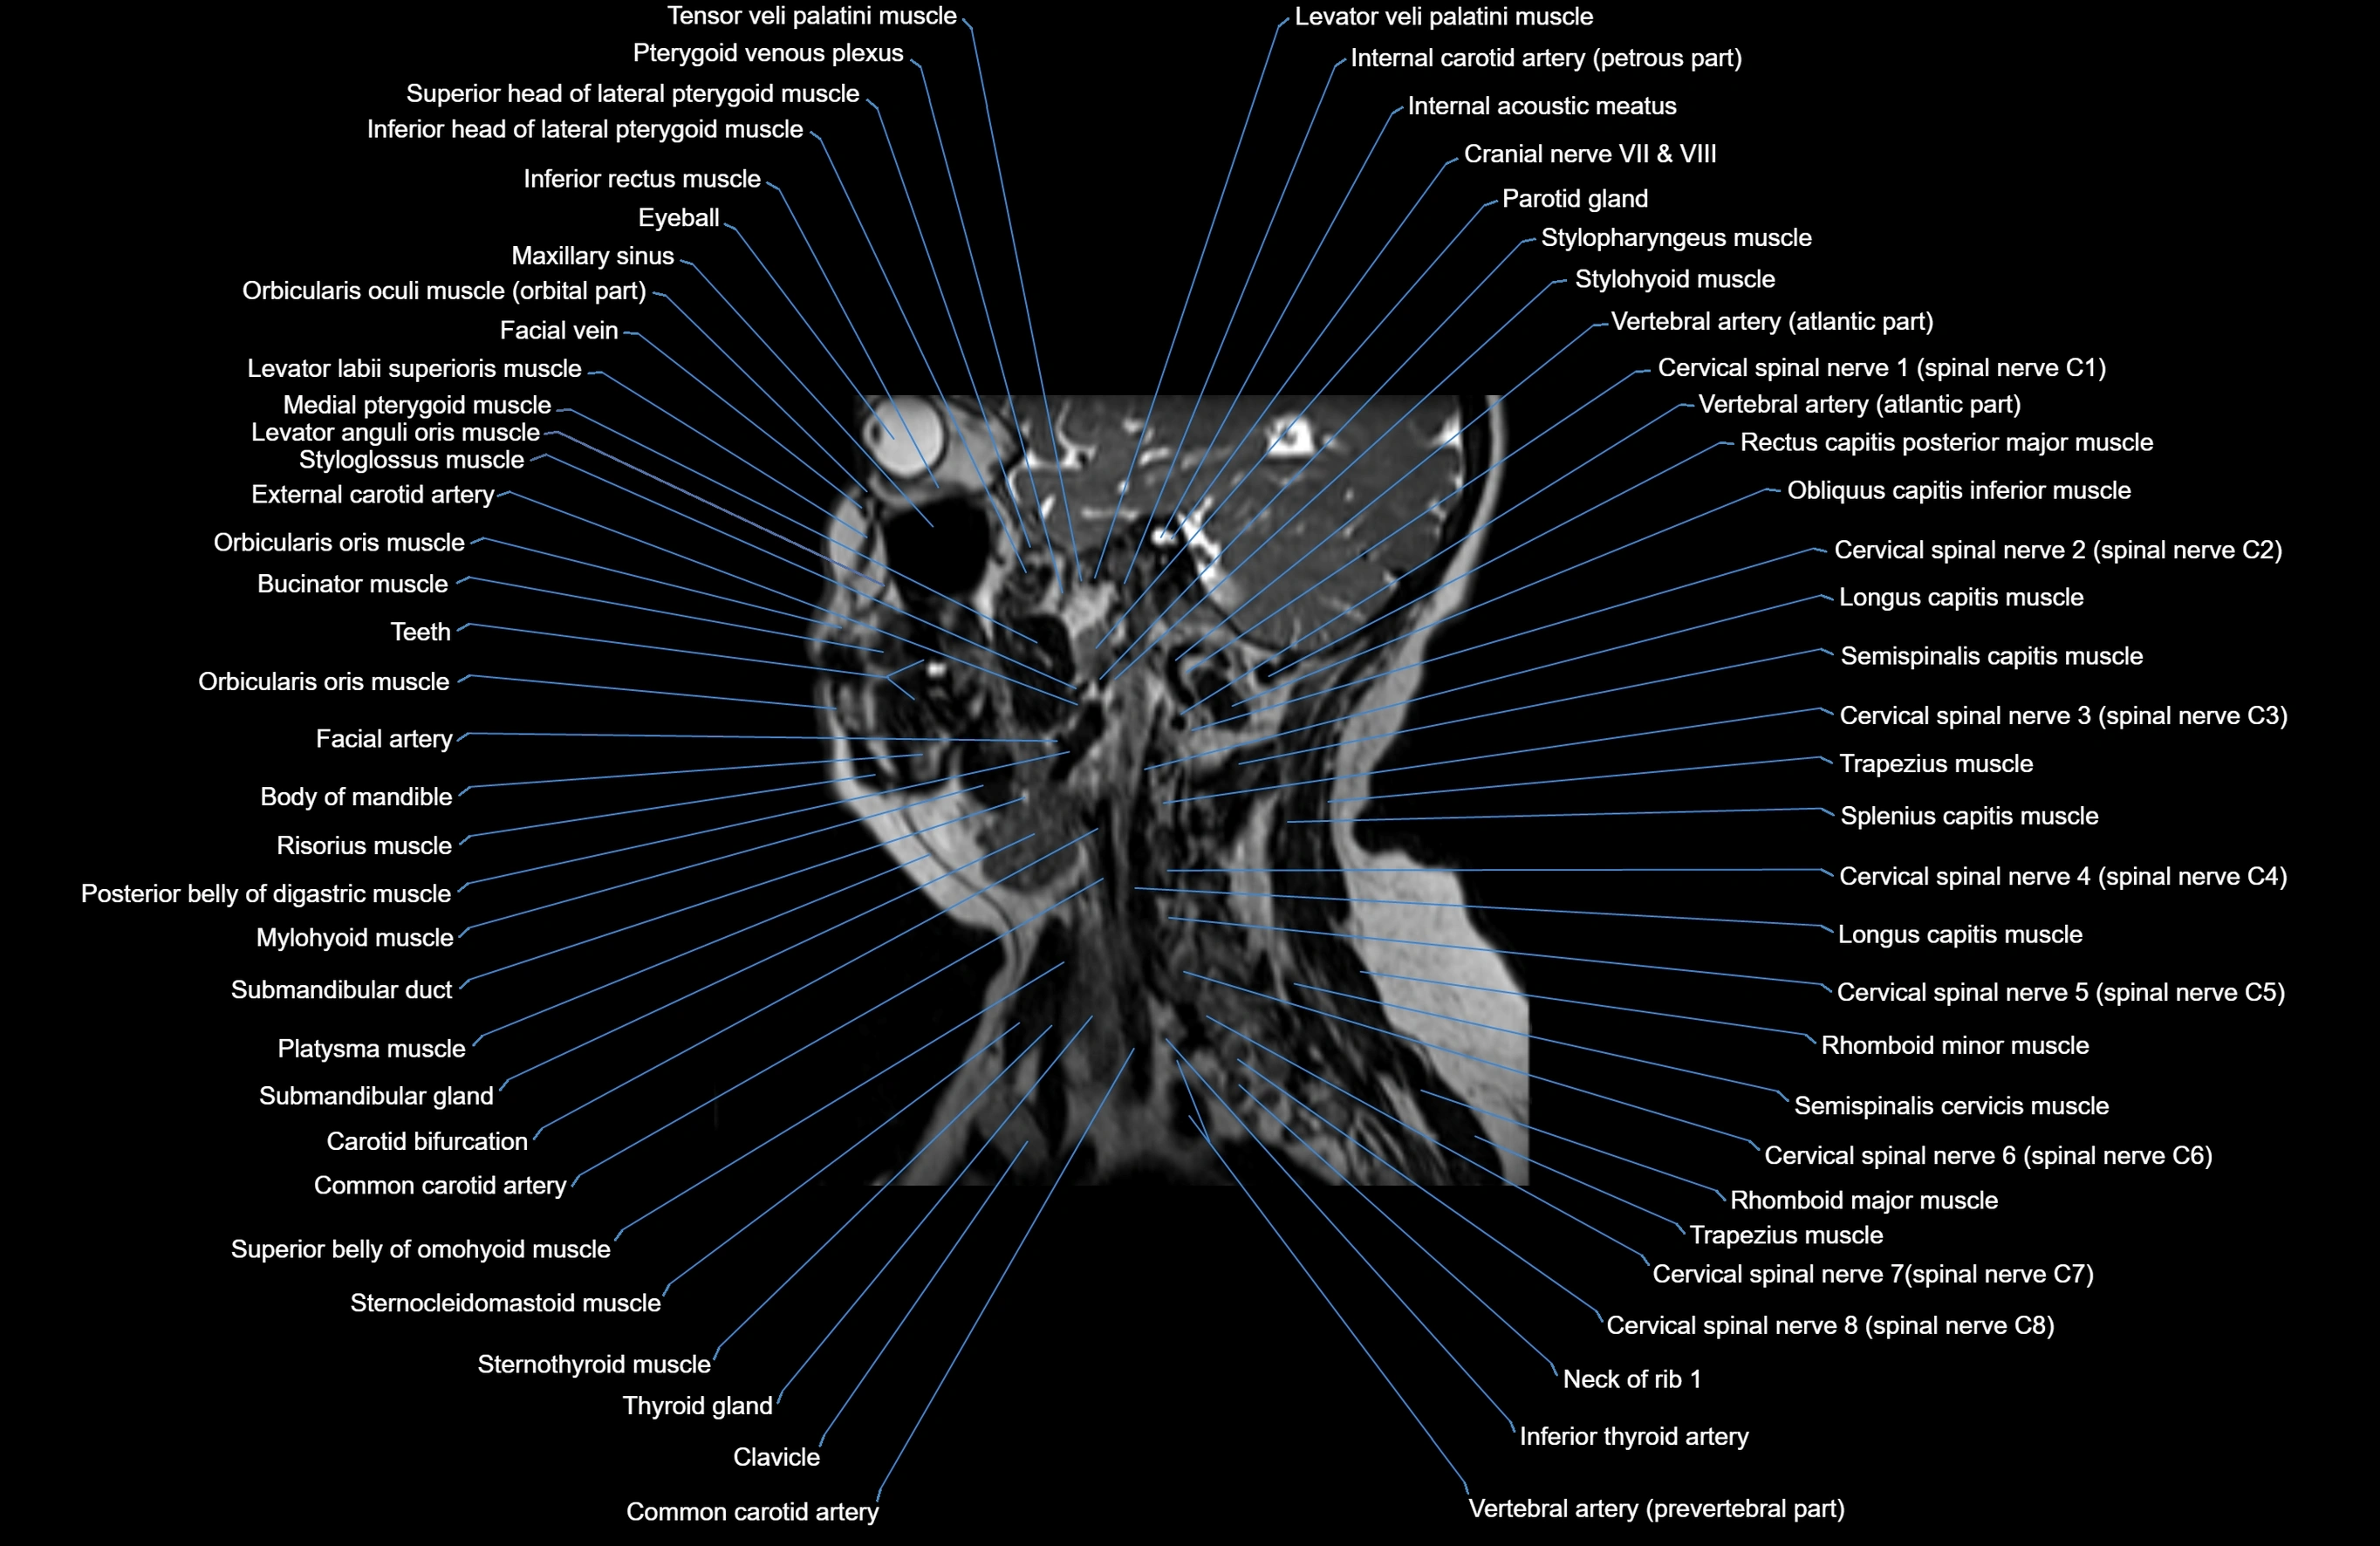

- Carotid bifurcation

- Cervical spinal nerve 1 (C1)

- Cervical spinal nerve 2 (C2)

- Cervical spinal nerve 3 (C3)

- Cervical spinal nerve 4 (C4)

- Cervical spinal nerve 5 (C5)

- Cervical spinal nerve 6 (C6)

- Cervical spinal nerve 7 (C7)

- Cervical spinal nerve 8 (C8)

- Clavicle

- Common carotid artery

- External carotid artery

- Inferior thyroid artery

- Platysma muscle

- Semispinalis capitis muscle

- Semispinalis cervicis muscle

- Splenius capitis muscle

- Sternocleidomastoid muscle

- Sternothyroid muscle

- Styloglossus muscle

- Stylohyoid muscle

- Stylopharyngeus muscle

- Submandibular duct

- Submandibular gland

- Thyroid gland

- Trapezius muscle